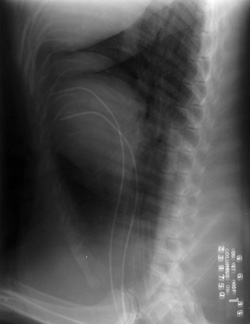

Double exposure during an angiocardiogram. This film was in a special automatic film changer, which jammed and did not move the film out of the way as it should have; therefore a double exposure occured.